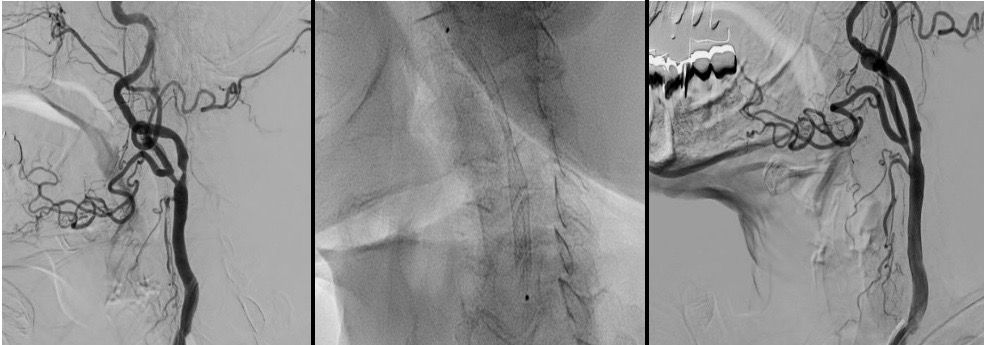

Tra queste, sono specializzato nel trattamento di stenting delle carotidi, una tecnica che consente di trattare in modo mini-invasivo il restringimento delle arterie carotidee, riducendo i rischi di ictus nei pazienti selezionati.